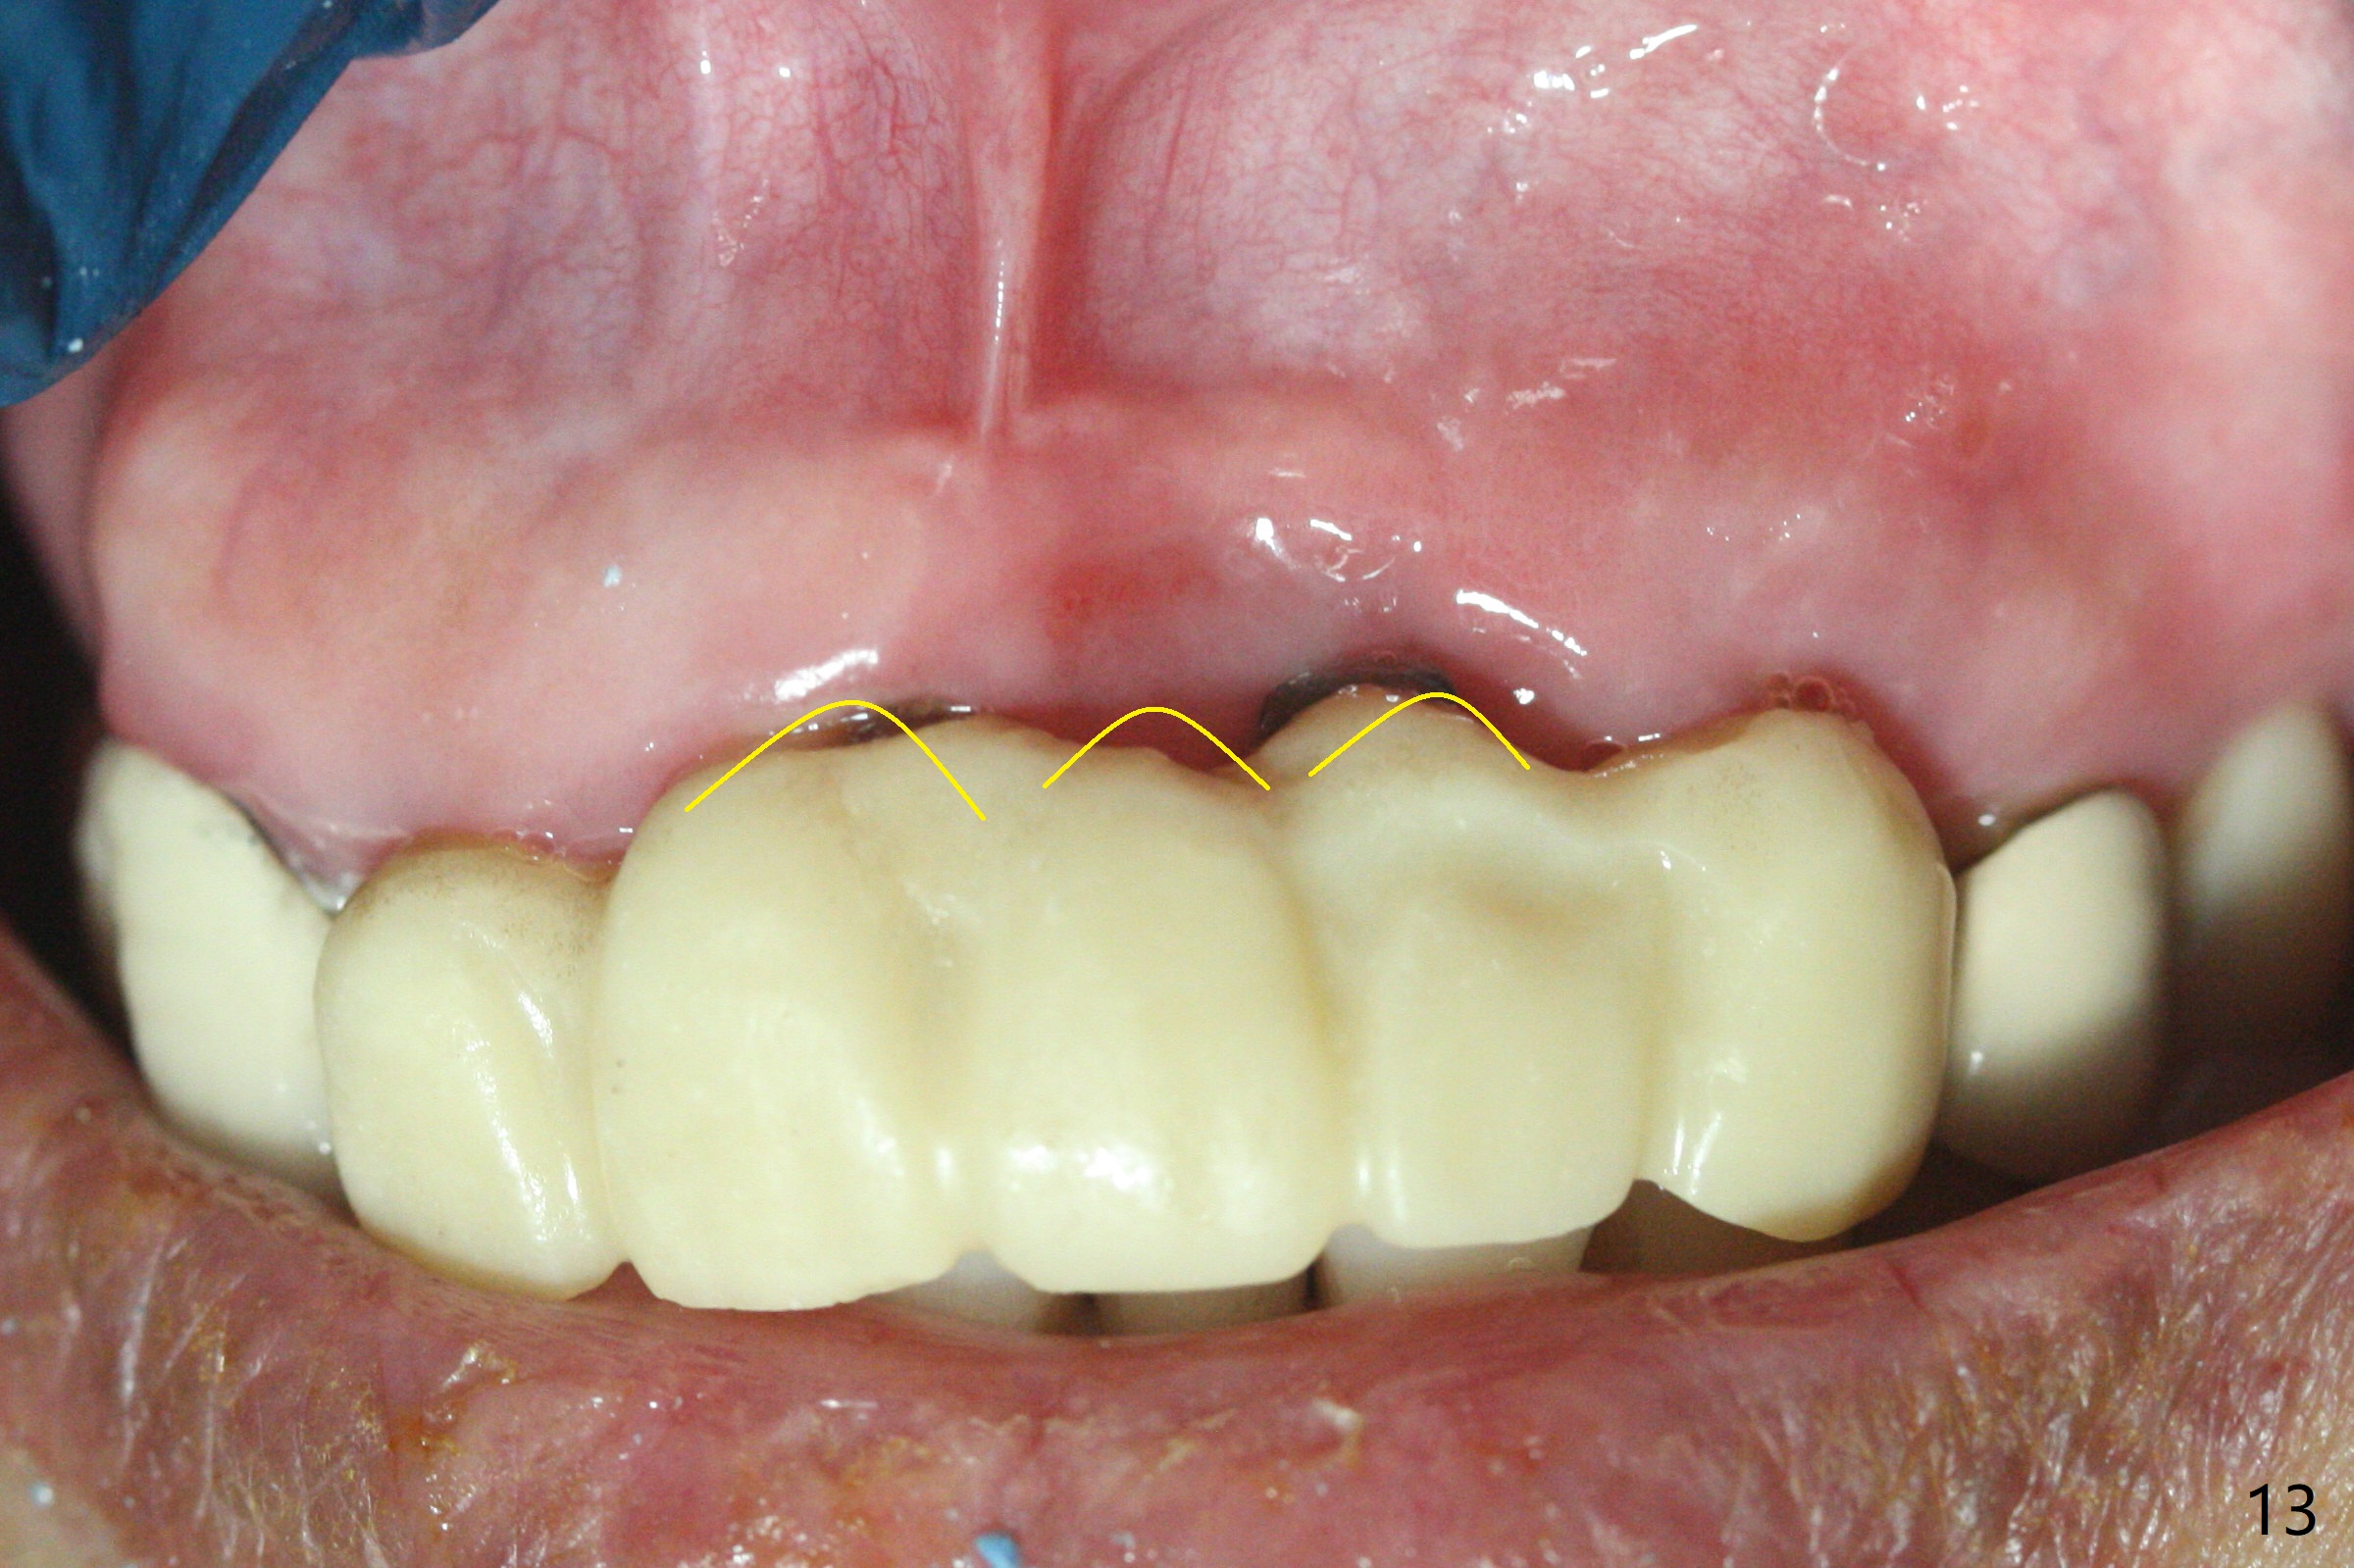

The mesiobuccal margin at #8 is redefined 4 weeks postop (Fig.14) so that the cervical end of the temporary crown is able to move mesially (Fig.13). The most coronal portion of the bone graft at #11 begins to be detached (*). The mesial portion of the abutment at #10 will be removed (curved white line) in the following week. After removing the most coronal portion of detaching bone graft at #11, acrylic is added to form a concave pontic (Fig.15 ^). With removal of the mesial portion of the abutment at #10, the retainer is moved distal (>). Pontics form at UL1 and 3 two months postop (Fig.16 *), while there is buccal atrophy at UL1,2 (Fig.17). 术后3个月植牙区牙龈形态良好(图十八),即将暴露,放置愈合基台。图十九是在右上1根管治疗时(基台放置后五天)拍摄。左上3术后3个月3个星期,1,2唇侧塌陷(图二十)。叶状植体处牙槽嵴往根尖萎缩(图二十一:^)。尽管做了松弛切口,放入事先预备的粘性骨粉后,几乎没有空间放置结缔组织移植物,恰好还没有取。放置PRF膜后,使用4-0 Monoglyc缝线缝合。牙龈似乎冠方移位(图二十二:箭头)。植骨后,唇侧仿佛饱满多了(图二十三:*)。骨粉放置于左上1,2唇侧和牙槽嵴(图二十四:*,与之前(图十九)对比)。后者有助于牙龈冠方移位,而前者有助于增加唇侧饱满度。植骨术后两周唇侧仍饱满(图二十五,六)。植骨后四个月牙冠粘固,两个月后,病人抱怨10号牙左右食物坎塞(图二十七),9/10牙冠撤除,10基台边缘加深,重做临时牙冠,同时增加9凹陷(pontic)。一个月后,9/10临时牙冠修整两次,11永久性牙冠撤除,也制备临时牙冠,外形明显改善(图二十八)。